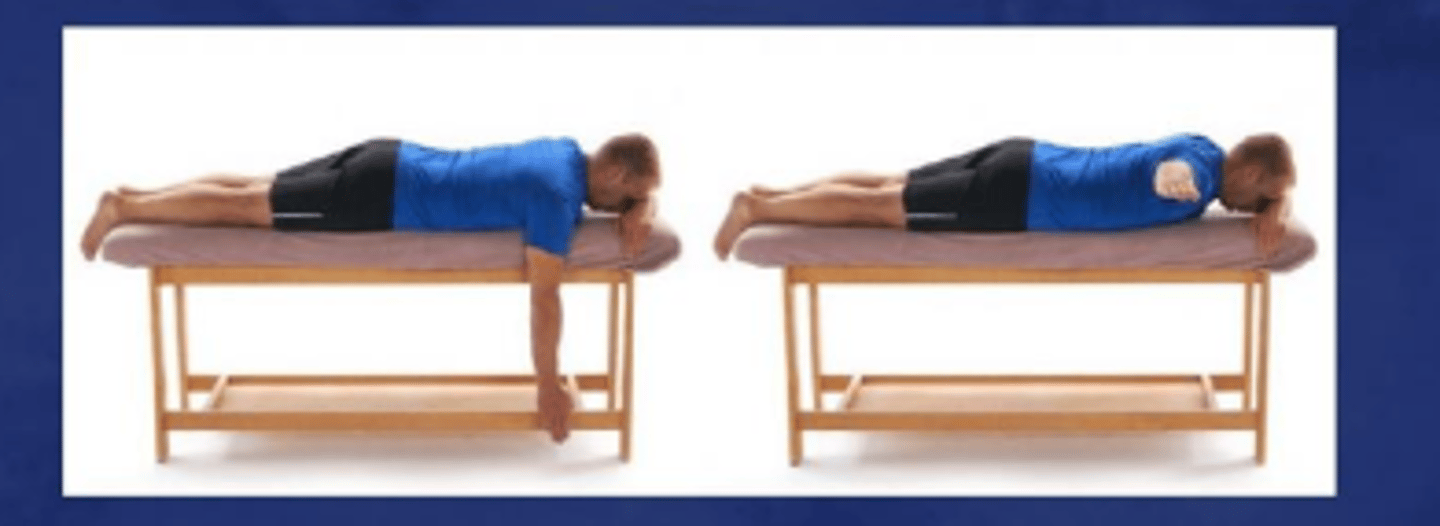

Prone horizontal abduction to neutral

What does the image show?